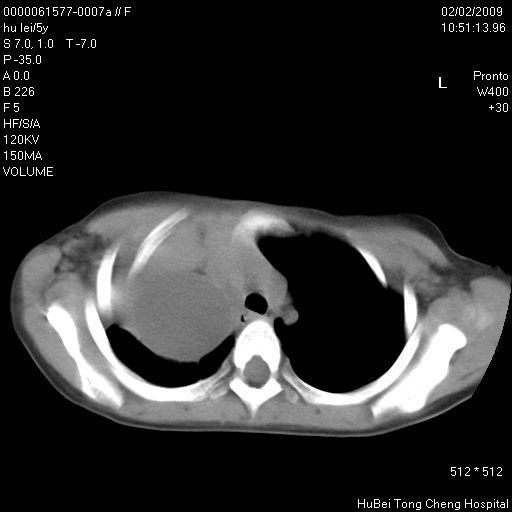

标题: PED1732:M5Y,右肺囊性占位!

患者:男,5。无明显不适,拍胸片考虑右肺囊肿。

行ct扫描,图象如下:

右肺巨大囊性占位性病变;考虑巨大肺囊肿,不排除淋巴管瘤可能。

病灶与前胸壁和右上纵隔、叶间裂界限不清,病灶前缘及内侧缘看不到正常的肺组织,不能排除包裹性积液。